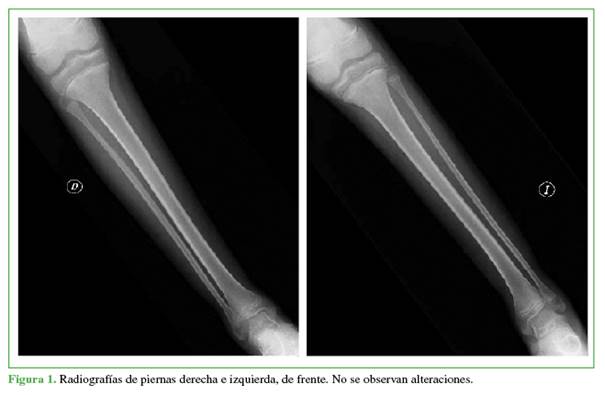

En el examen físico, el estado general era regular, tenía palidez cutánea y de mucosas generalizada; miembros inferiores simétricos, edemas grado 2 (depresión hasta 4 mm y desaparición en 15 min), abundantes petequias y hematomas de diferentes estadios evolutivos, movilidad de miembros inferiores levemente dolorosa, articulaciones móviles sin signos de flogosis, marcada debilidad muscular. El examen neurológico fue acorde a su edad; signo de Romberg negativo, fuerza 3/5 bilateral, marcha con aumento del polígono de sustentación, lograba dificultosamente la bipedestación con asistencia. Los análisis bioquímicos al ingresar arrojaron los siguientes resultados: anemia normocítica e hipocrómica (hematocrito 23%; hemoglobina 7,5 g/dl; leucocitos 5,50 mil./mm3; volumen corpuscular medio 75,4 fl; hemoglobina corpuscular media 24,6 pg; recuento plaquetario 306 mil./mm3; proteína C reactiva 0,8 mg/l). Se tomaron radiografías de huesos largos, de frente (Figuras 1 y 2).